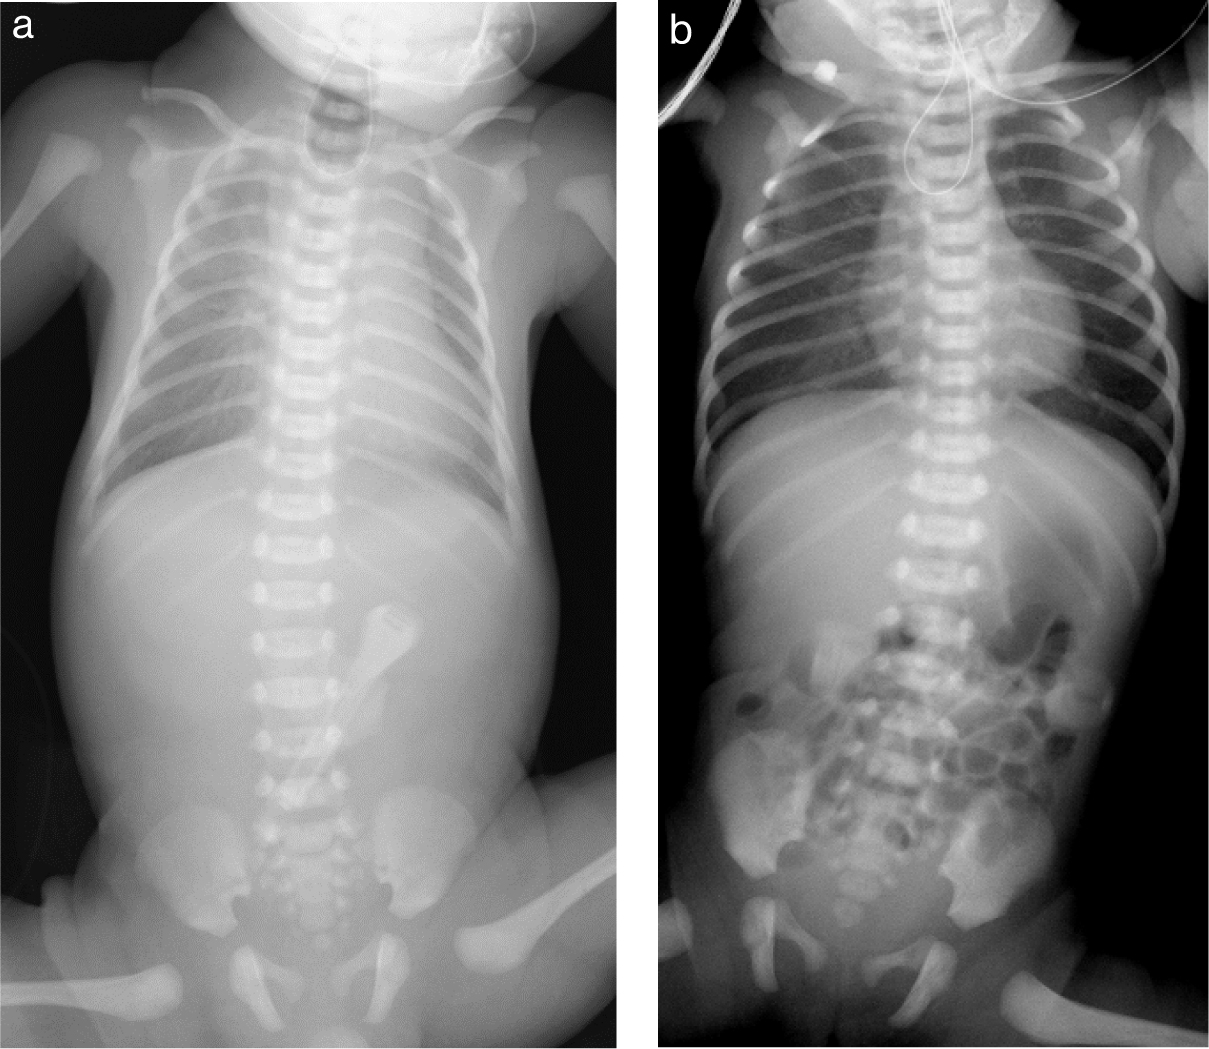

2. 画像所見胎児期に診断がつくことは稀で,出生後の腹部膨満,胎便排泄遅延などの臨床症状や身体所見が最も重要.出生後の画像検査では腹部レントゲンで典型例において結腸に限局性の拡張ガス像を認めることがあるが,病変の長さなどによっても所見は様々であり,注腸造影により病変部である遠位側腸管の狭小化と口側腸管の拡張によって作られる口径差(caliber change)の確認が非常に重要(Fig. 6).初回の造影ではcaliber changeが不明瞭であることもある.

a.Rectosigmoid型ヒルシュスプルング病の出生時腹部レントゲン写真.限局的に拡張した結腸ガス(*)を認める.骨盤内にはガスを認めない.

b.別のRectosigmoid型ヒルシュスプルング病症例の出生時腹部レントゲン写真.腹腔内にびまん性に拡張したガス像を認める.

c.Rectosigmoid型ヒルシュスプルング病の注腸造影所見.遠位側の狭小腸管と近位側の拡張腸管を認め,口径差(caliber change)(矢印)が明瞭に描出されている.